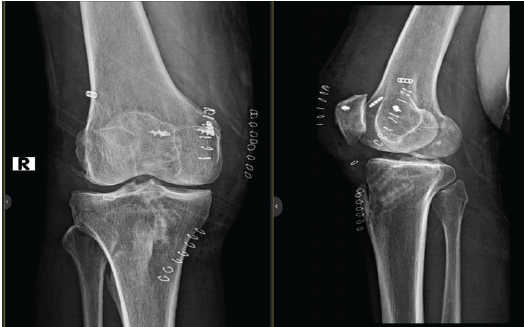

Immediate Post-op X-ray of right knee was done which showed stable fixation and satisfactory alignment. ( Fig. 8)

Figure 8: Immediate post-operative X-ray of right knee.